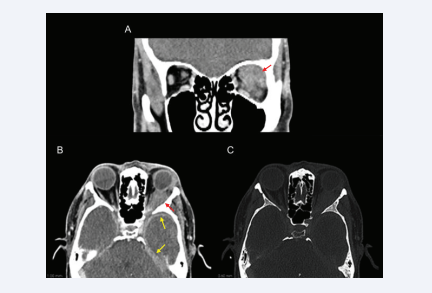

A 58-year-old man with a medical history of hypertension, controlled with candesartan and hydrochlorothiazide, and surgical history of left eye cataract surgery using retrobulbar anesthesia 1 month prior presented with complaints of blurry vision and headaches since the surgery. Ophthalmologic examination revealed left proptosis, chemosis and limitation of upwards and downwards eye gaze, without diplopia. A central scotoma and hyporeactive left pupil were also documented without clear relative afferent pupillary defect. Routine laboratory results were unremarkable. Urinalysis did not show proteinuria or hematuria. Computer tomography (CT) (Figure 1), and magnetic resonance imaging (MRI) (Figure 2), were performed that revealed a left intraorbital infiltrating soft tissue lesion with involvement of the superior and lateral rectus muscles and extension into the preseptal space, involving and enlarging the lacrimal gland.

CT scan demonstrating a soft tissue density mass in the left orbit infiltrating the post-septal intra and extra-conal spaces in the left superior  quadrant (A and B; red arrow) with antero-lateral extension to the left lacrimal gland and posterior extension to the cavernous sinus. Intracranially,  bilateral left predominant temporal and tentorial pachymeningeal can also be noted (B; yellow arrow). No bony destruction was documented (C).

Figure 1: CT scan demonstrating a soft tissue density mass in the left orbit infiltrating the post-septal intra and extra-conal spaces in the left superior quadrant (A and B; red arrow) with antero-lateral extension to the left lacrimal gland and posterior extension to the cavernous sinus. Intracranially, bilateral left predominant temporal and tentorial pachymeningeal can also be noted (B; yellow arrow). No bony destruction was documented (C).